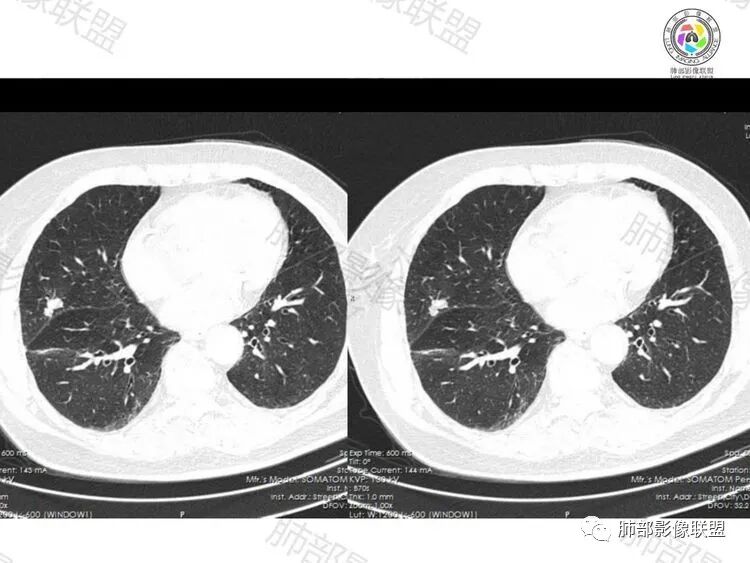

右肺叶裂旁实性结节,边缘平直,部分收缩、凹陷,似有两个子灶融合,呈葫芦样改变,边缘可见磨玻璃影,及血管有轻度牵拉,无增强,考虑:炎性(隐球菌),建议短期随访及隐球菌荚膜实验,必要时穿刺。

右中肺结节,光滑,两结节融合,支气管旁边穿行,斜裂轻微牵拉,没毛刺,没ggo,考虑肉芽肿炎(隐球菌?),建议完善隐球菌荚膜实验,鉴别腺癌

老年女性,右肺中叶结节,光滑,两结节融合,结节可见膨隆,收缩,边缘平直,斜裂受牵拉,边缘长毛刺,边缘模糊的ggo,总体考虑炎性病变,隐球菌?结核?,就是担心肿瘤合并炎性病变,建议其他检查或治疗后复查。

巴伟:右肺中叶结节,边缘膨隆为主,局部平直,支气管截断,叶间裂牵拉,似见多个小结节,首先考虑恶性,腺癌可能大,鉴别炎性结节,隐球,结核。薏米:

右肺中叶结节,有凹陷,有膨隆,空泡,邻近胸膜叶间胸膜可见小结节,考虑恶性,腺癌可能,鉴别肉芽肿性炎症